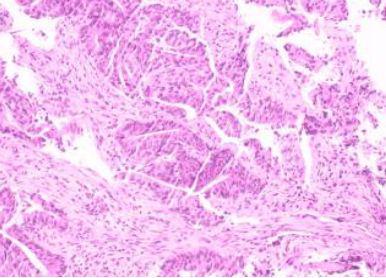

病理提示直肠腺癌!这个消息让王大哥和家人一时难以接受,他们怎么也没想到,原本以为只是小小的痔疮问题,竟然会是癌症。

直肠占位病理

看到病理结果,林燕第一时间与王大哥的家属进行详细沟通,让他们对病情有更全面地了解。经过慎重考虑,家属决定进行手术治疗。术后,病理结果显示王大哥的肿瘤为中分化腺癌,幸运的是,切缘均为阴性,也没有发现远处转移的迹象。这个消息让王大哥和家人松了一口气,心中燃起了希望的火花 。